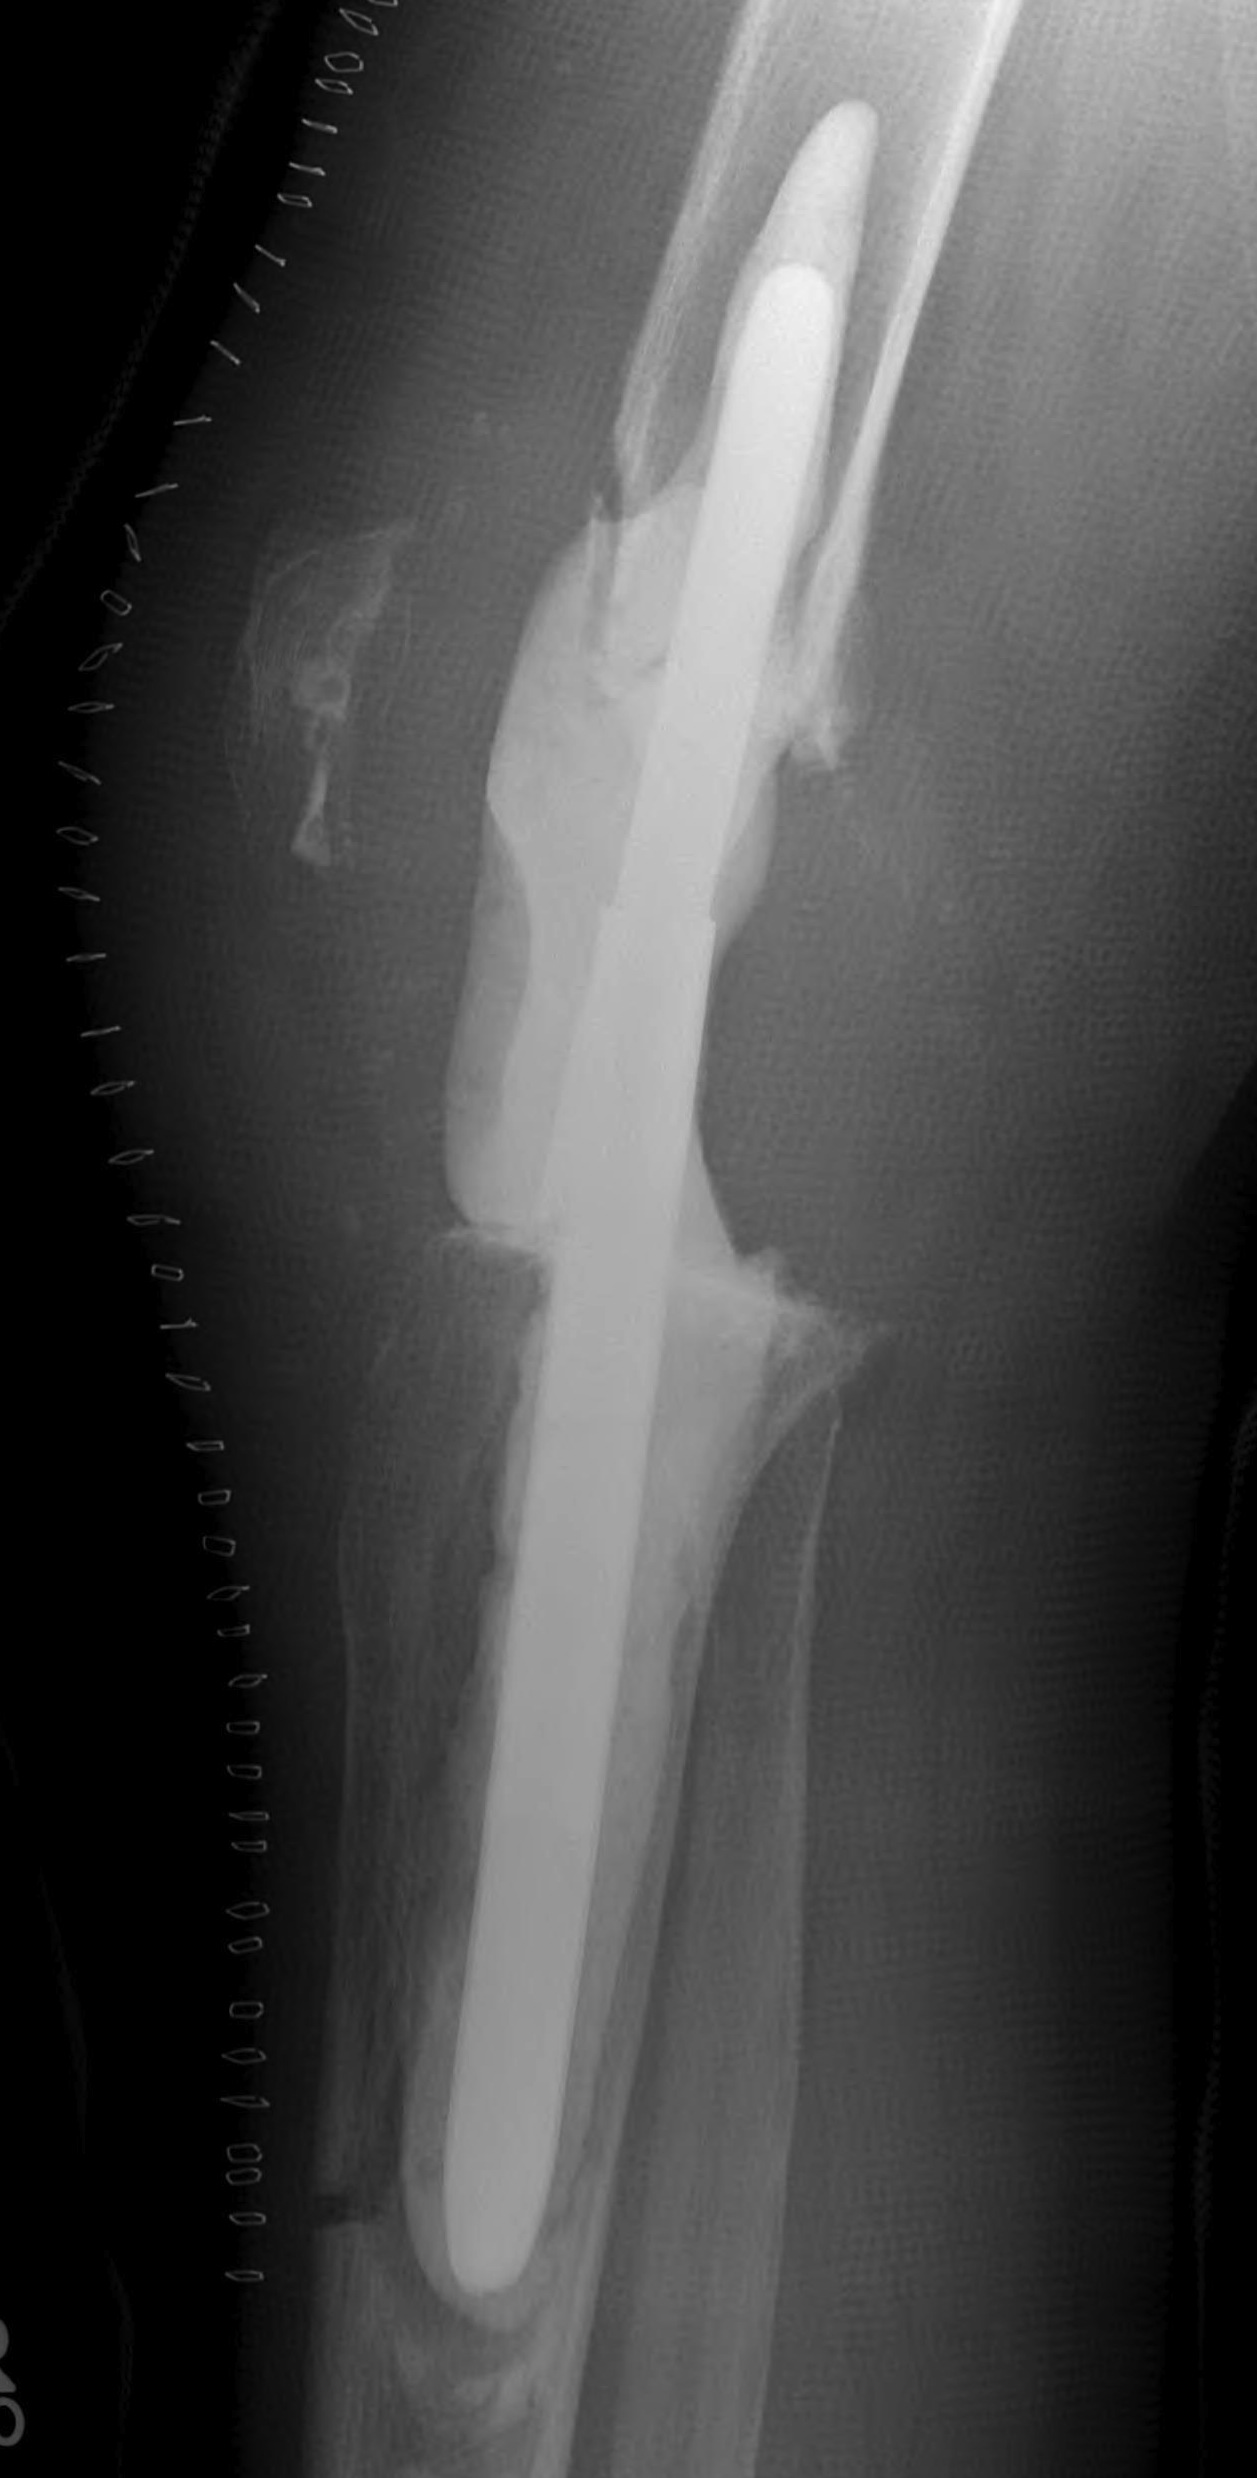

- 184 cemented revision TKR with press fit stems

- significant bone loss

10. Loosening